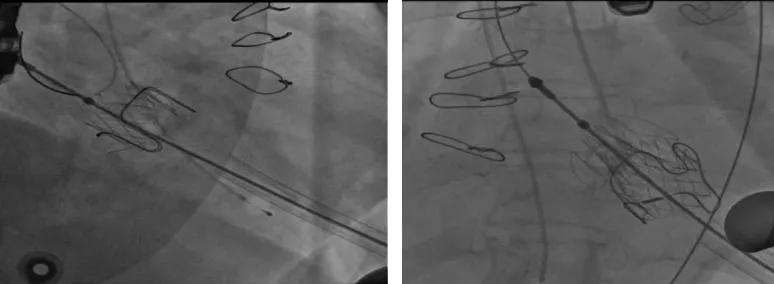

9:30,手术开始,在起搏器保驾护航下,在超声引导下,经左胸心尖切口,由于患者二次手术,加上长期心衰、组织水肿,心包粘连严重,心肌薄,解剖难度大,郑建杰教授与姜益医生精准配合,成功分离组织,在X-线透视下释放定位键,于原生物瓣膜支架凹槽“镶嵌”、释放,几乎一瞬间完成了“25mm 二尖瓣瓣中瓣换瓣”操作。

10:00,进行主动脉瓣置换。导丝避开二尖瓣瓣下腱索及周围定位键,因患者主动脉窦管交界只有28mm,故选择主动脉窦内释放定位键,最大限度将瓣膜降入左室流出道,超声、X-线定位,下拉释放瓣膜,观察位置合适无移位。手术结束,二尖瓣植入仅用时15分钟,主动脉瓣植入耗时18分钟,33分钟创造生命的奇迹。术中出血少、无传导阻滞、无流出道梗阻,生命体征平稳。术后超声显示瓣膜反流消失,新植入的瓣膜运行良好,流速正常。